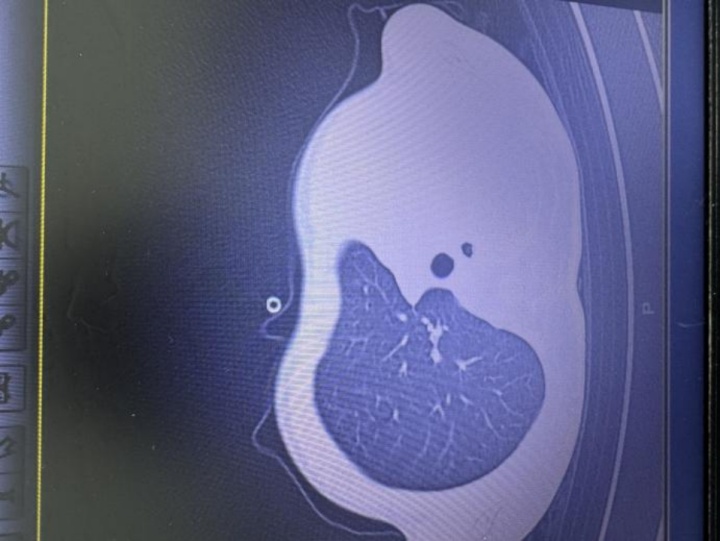

急诊检查结果让医护人员瞬间紧张:验血显示炎症指标大幅上升,胸片更发现左侧肺叶几乎“不工作了”,影像学中变成大片白色,肺功能严重受损。孩子已经缺氧,随时有窒息危险。

图:影像显示肺白了一半